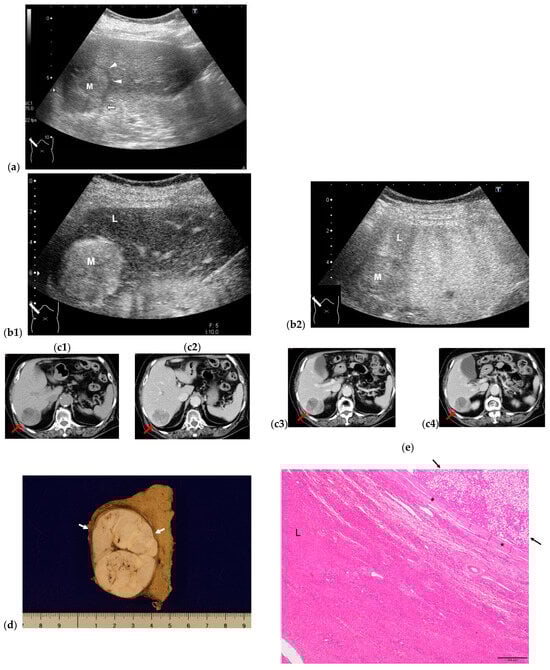

- Naganuma, H.; Ishida, H.; Ogawa, M.; Sato, T.; Sageshima, M.; Suzuki, K.; Ohyama, Y. Hetaocellular carcinoma in otherwise sonographically normal liver. J. Clin. Ultrasound 2019, 47, 325–330. [Google Scholar] [CrossRef] [PubMed]